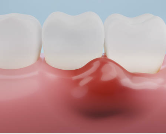

✅ 1. 양치할 때 피가 자주 난다

치은염의 가장 흔한 증상이에요.

잇몸이 염증으로 인해 혈관이 약해지고 예민해지면,

조금만 자극이 닿아도 쉽게 피가 나요.